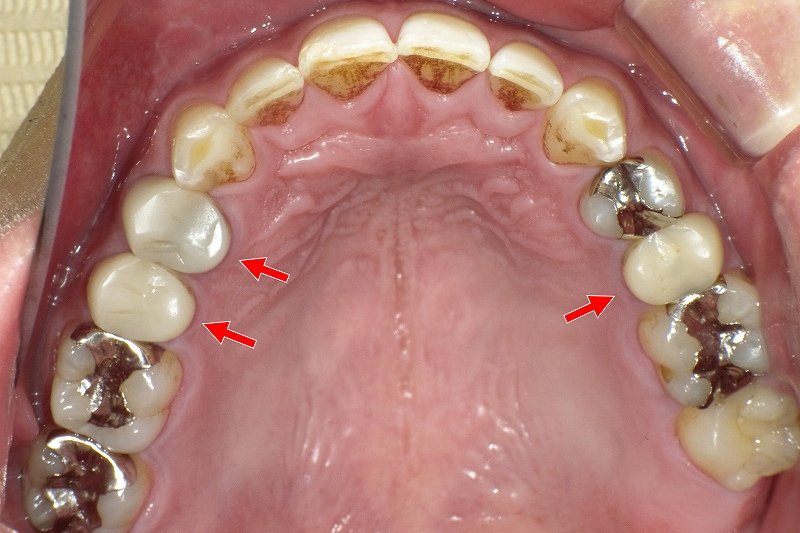

従来の保険診療では、奥歯の被せ物は金属冠(いわゆる銀歯)が主流でしたが、CAD/CAM冠の導入により、金属を使用しない白い補綴治療が保険の範囲内で可能となりました。これにより、審美性と生体安全性の両立が図れる治療選択肢として広く普及しています。

これに対しCAD/CAM冠は、金属を使用せず自然な白さを再現できる点が大きな特徴です。患者の審美意識の高まりや金属アレルギーへの配慮といった社会的背景を受け、診療報酬改定を通じて段階的に保険適用範囲が拡大されてきました。